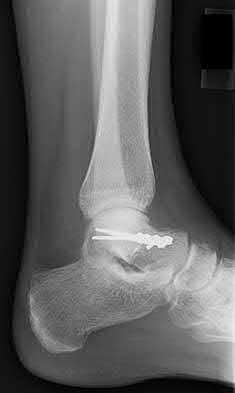

4. # After undergoing the treatment seen in Figure A, when should a patient be expected to safely operate the brakes of an automobile?

1. 6 weeks

2. 2 -4 weeks

3. 6 months

4. 8-9 weeks

5. 3 months

Corrent answer: 4

Figure A shows a patient after an open reduction and internal fixation of a bimalleolar ankle fracture.

Egol et al showed that by nine weeks, the total braking time of patients who had undergone fixation of a displaced right ankle fracture returns to the normal, baseline value.

Egol et al, also found that appropriate braking time returns at a point 6 weeks after initiation of weightbearing after treatment of lower extremity long bone and periarticular fractures, as examined with a driving simulator. No differences were seen in return of braking time between periarticular fractures and long bone injuries.